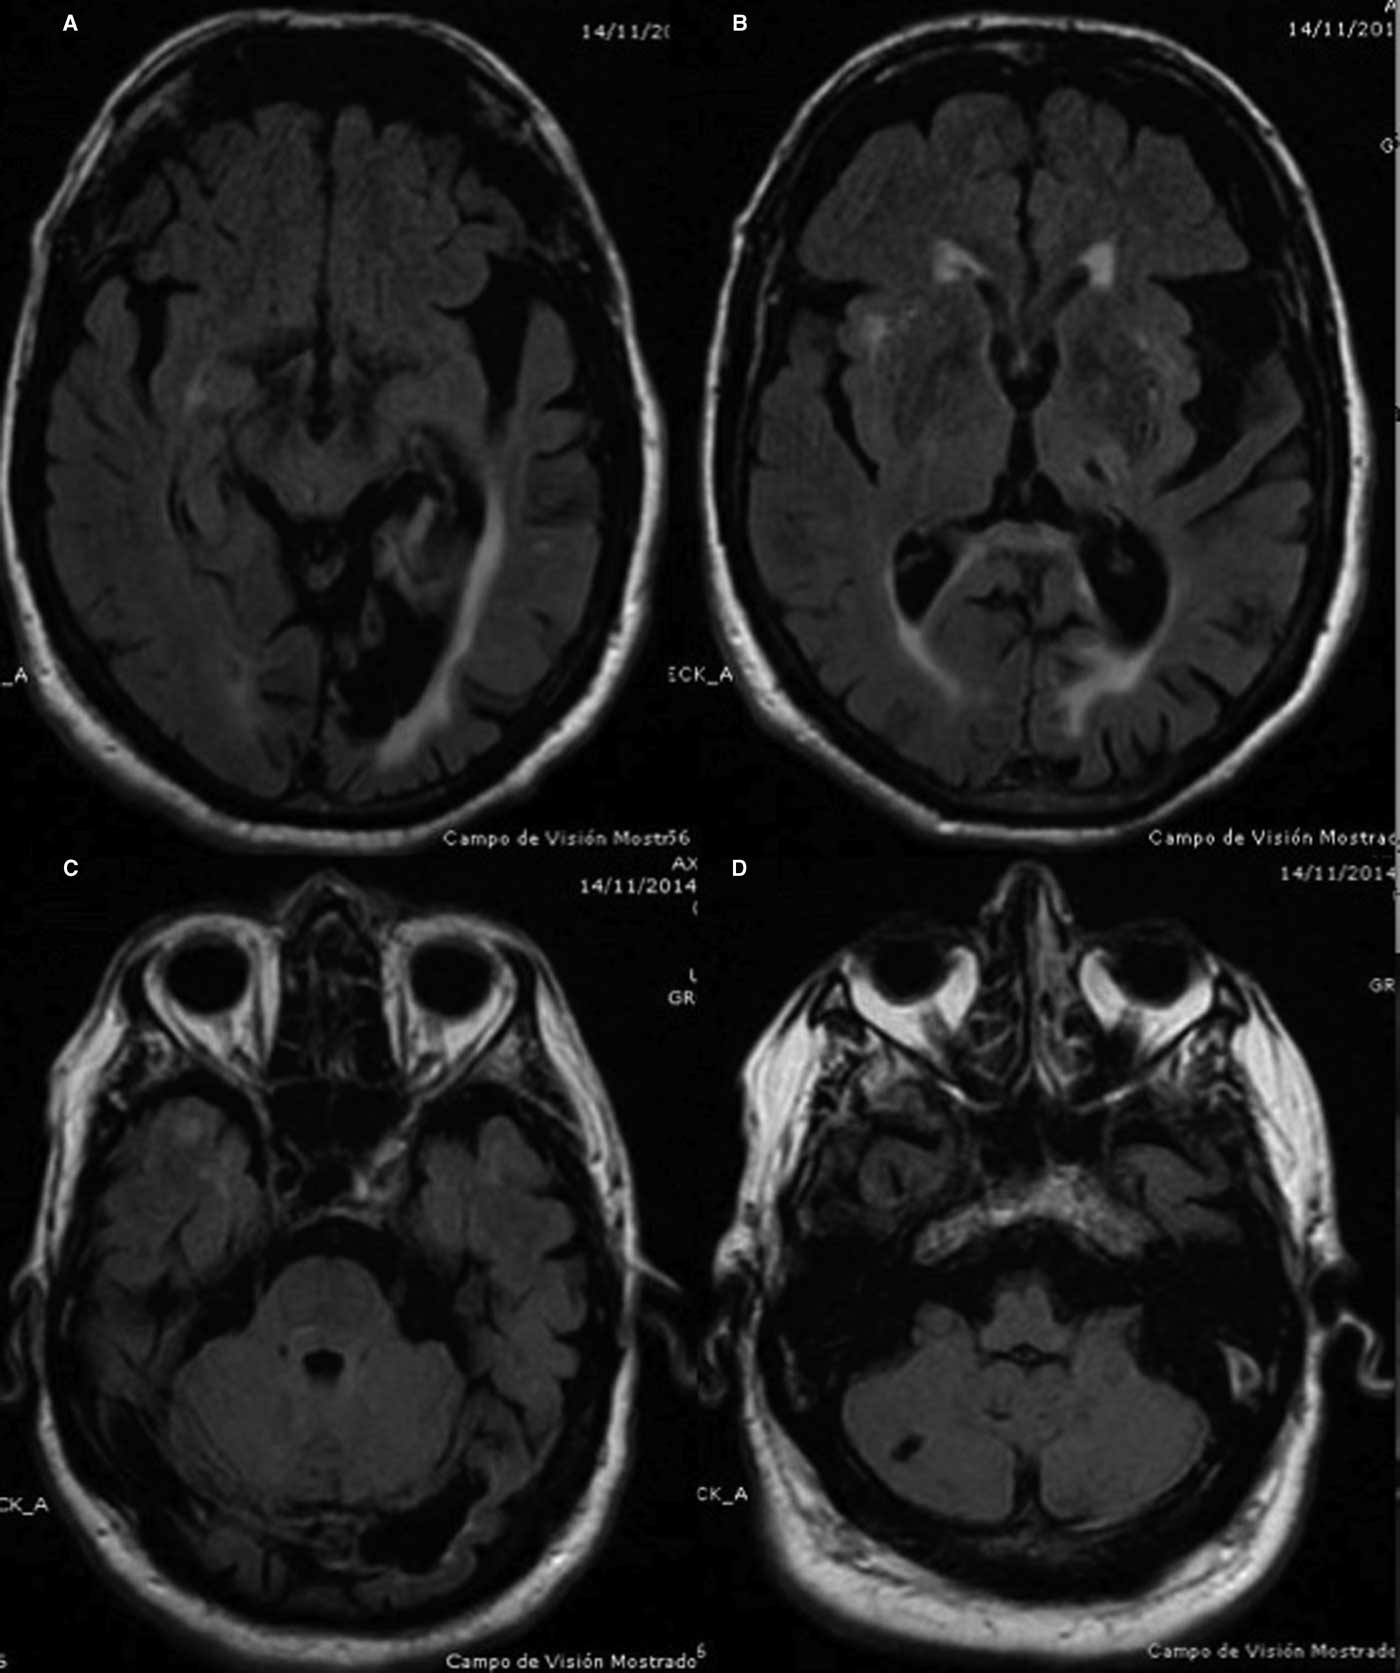

In 2014 clinical examination prior to beginning dopaminergic treatment demonstrated a bilateral tremor with inconsistent characteristics in his upper limbs: a coarse, irregular, low frequency resting tremor in the right arm which was accentuated by posture and further increased by goal-directed movements; on the left side, he had classic parkinsonian rest hand tremor without postural or intention tremor (video 1, segments 1-4). In addition, the patient had right homonymous hemianopia examined by confrontation, dystonic posturing in the right hand, mild hypomimia, chin tremor, and bilateral mild rigidity and bradykinesia (video 1, segment 5). Electromyographic recordings revealed alternating contraction of agonist and antagonist muscles of the left upper limb during the resting limb position at a frequency of less than 6 Hz and an irregular tremor at rest, at lower frequencies in the right arm (Figure 1). There was no co-contraction of the agonist-antagonist muscles in the right upper limb. Cranial MRI revealed left parieto-temporal atrophy with left ventricular ectasia, encephalomalacia in the left posterior cerebral artery territory, small infarction in the right cerebellum and lacunar infarction in the left thalamus (Figure 2 A-D). Single-photon emission computed tomography with I123 ioflupane (DaTSCAN) demonstrated a marked dopaminergic deficiency in the bilateral striatum (figure 3). PD was diagnosed and the patient received levodopa, reaching a final dose of 750 mg/day with positive response of the three components of HT. Rest tremor in the left arm, chin tremor and other parkinsonian symptoms (rigidity and bradykinesia) were slightly improved.

Figure 2 Axial FLAIR cranial MRI images.